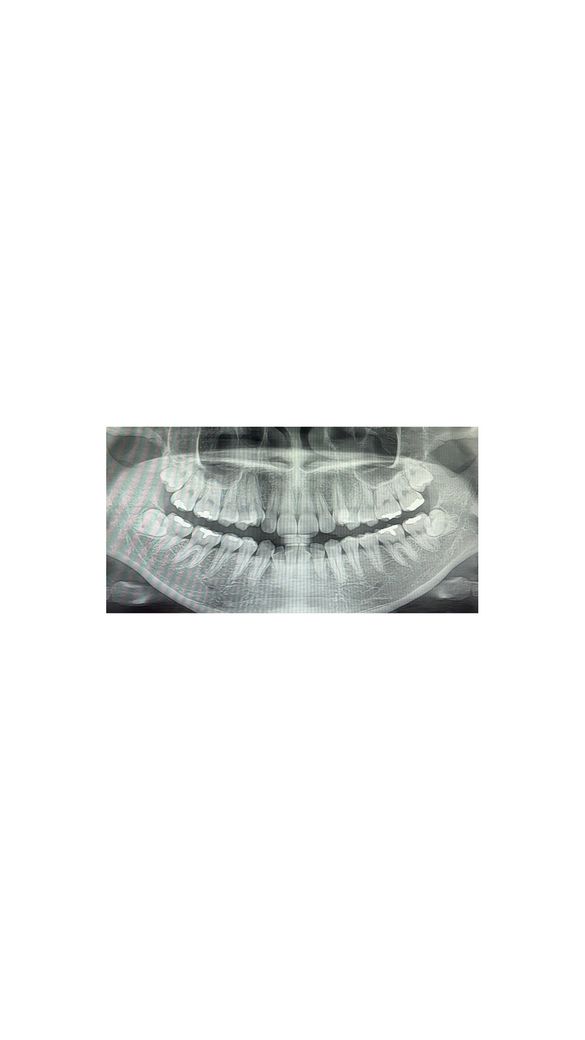

덧니 교정 상악 발치 필수인지 봐주세요 ㅜㅜ

치아 사진 있습니다

병원 두군데 진료받았는데 둘 다 위 송곳니 덧니 뒤 치아 하나씩 발치하고, 한 군데는 아래 발치 여부는 제 선택, 다른 한 군데는 아래는 발치 없이 총 2개 발치하자고 하셨습니다

지금은 아래 어금니가 위 어금니보다 뒤에 있는 상태구요

아래턱이 작고 들어가있고 외관상 문제가 없으니 아래는 발치하지 말자고 하셨어요

상악 2개는 교정기 부착 2-3개월 후 발치하자고 하셨고, 사랑니 4개도 교정 중간에 발치하자고 하셨구요

돌출입이 심하지 않은데 위 치아 발치를 꼭 해야하는 케이스일까요??

엑스레이 상이나 구강 사진을 보면 덧니가 심한상태라 치아를 이동시킬 공간이 부족해 보이긴합니다. 발치교정이 필요 할것처럼 보입니다.